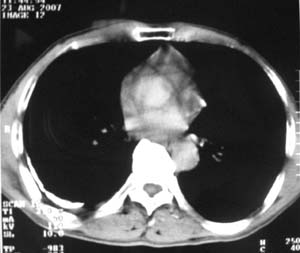

标题: CT9556:男,54岁,包裹性积液,请各位老师会诊其原因! [打印本页]

男,54岁,无任何不是感.体检发现右肺部阴影.现行ct进一步确诊.

右侧胸廓塌陷,肋间隙变窄,肋骨增生变粗,脏壁层胸膜肥厚、钙化。符合陈旧性结核性脓胸改变

右侧包裹性积液并胸膜钙化,性质还是结合穿刺细胞学检查的好,结核性、化脓性均会有钙化。